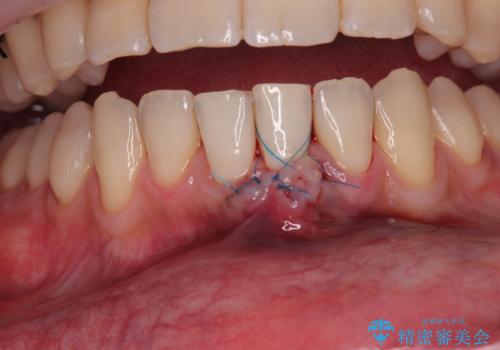

- 他院で矯正治療を終えた結果、下顎前歯の歯肉が退縮してしまい、歯根が見えていることが気になるとのことで来院された患者様です。

歯肉退縮に対して、上顎からの結合組織移植術(CTG)により、歯根の被覆を行うとともに、歯肉の厚みを増すことで将来の退縮リスクを抑制することとしました。

被覆量が不十分の場合には、追加で手術を行うことで患者様の了解を得ました。